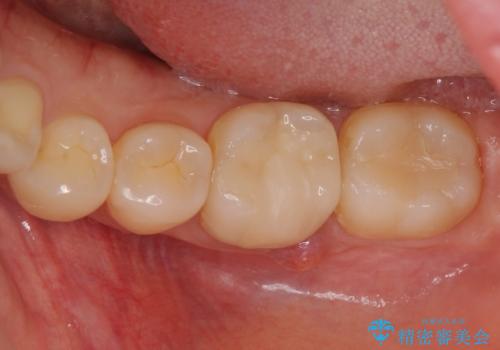

奥歯が痛い。精密根管治療〜オールセラミッククラウン

奥歯の根管治療~オールセラミッククラウン